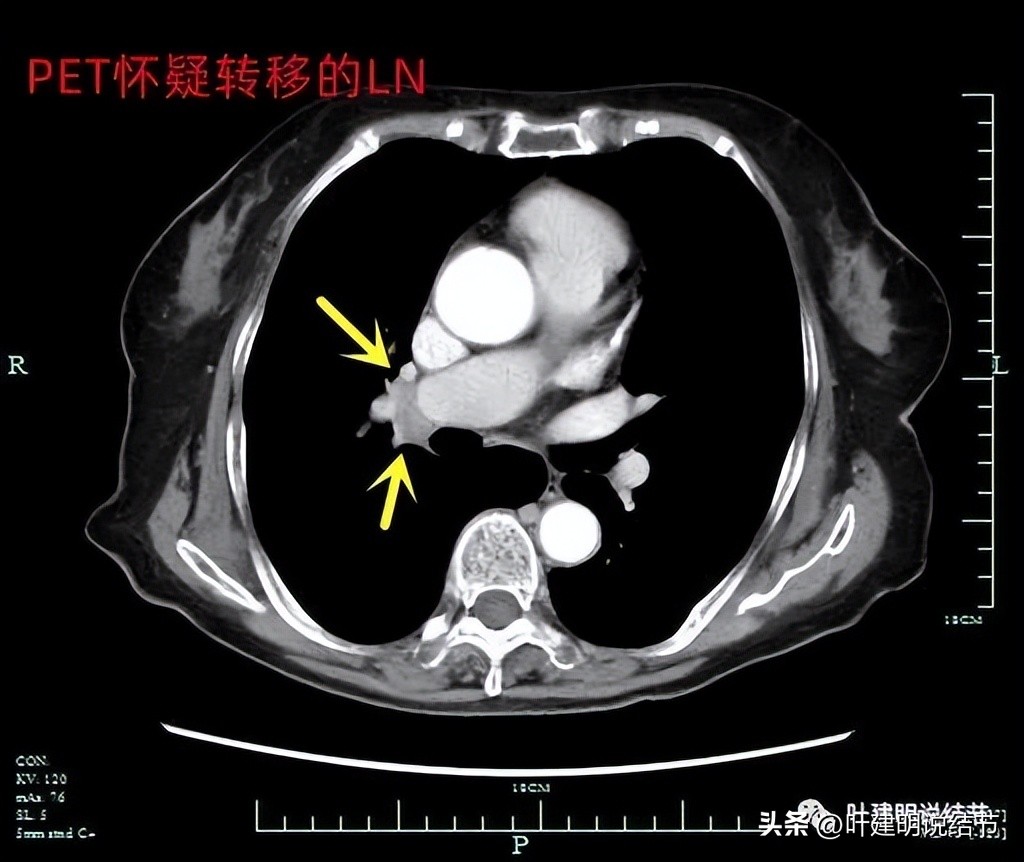

腔静脉旁有肿大淋巴结(黄色箭头)。

上图是PET-CT怀疑转移的淋巴结,跨在肺动脉上(跨在尖前干的上方)